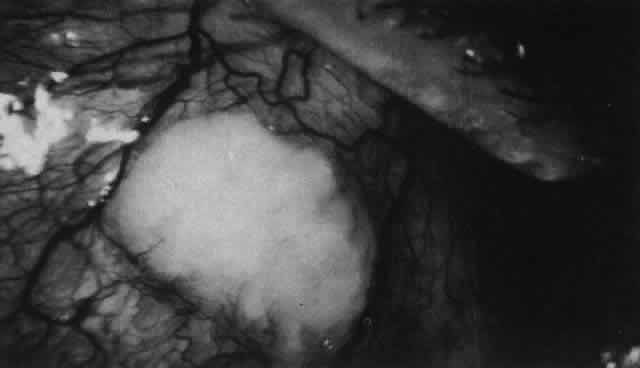

The anterior sclera loses its covering of episclera and develops an area of yellow-white necrotic slough over many months; this eventually separates or is absorbed, leaving the underlying choroid covered by either conjunctiva or nothing at all. As with necrotizing disease, the choroid does not bulge into this ectatic area; but unlike necrotizing disease, spontaneous healing of even small perforations is very limited once the necrotic tissue has been removed (see Fig. 50). Fluorescein angiography is not helpful, except to indicate areas of vascular closure in an otherwise extremely thin, atrophic episcleral tissue.4 The formation of a sequestrum appears to be caused by arteriolar closure as opposed to the venular disease seen in the other forms of necrotizing scleritis. Posterior Scleritis Because the posterior sclera is invisible, the diagnosis of posterior scleritis is made only if the anterior sclera is also involved or some other sign or symptom leads one to suspect it. Posterior scleritis is much more common than previously suspected, as recent clinical and pathologic studies have shown.19,28,29 There are two distinct forms of posterior scleritis. The first is usually associated with an anterior scleritis. This granulomatous disorder, like its anterior counterpart, can be diffuse, nodular, or necrotizing in character and is associated with the connective tissue diseases. The second form occurs in young patients of all races who are 9 to 40 years of age. It is always diffuse in character but is not associated with any systemic disorder. Both forms may cause uveitis if the inflammation affects the ciliary body, and in both forms the patient may develop exudative retinal detachments, choroidal folds, and swelling of the disc (Figs. 51 and 52). The granulomatous type may also involve the structures outside the globe, causing proptosis (Fig. 53), limitation of ocular muscle movement, and, uniquely, retraction of the lower lid on attempted elevation of the eye (Fig. 54). Diagnosis is with B-scan ultrasonography. TREATMENT Scleritis is almost always accompanied by very severe pain that prevents sleep. A response to treatment is heralded by a dramatic relief of pain even though the condition might appear to be getting worse (Figs. 55 through 59). Treatment may be modified with confidence once the pain has disappeared.